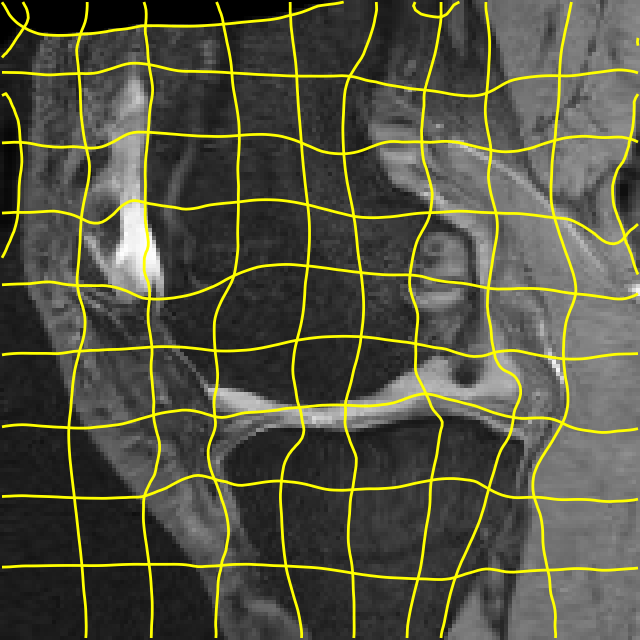

Moving

Target

Mono-0

Mono-5

DA-1

DA-5

Mono-200

Results: All trained networks are evaluated using Dice overlap scores between predictions and the manual segmentations for the segmentation network, or between the warped moving segmentations and the target segmentations for the registration network. Tabs. 1 and 2 show results for the knee and brain MRI experiments respectively in Dice scores (%). Fig. 2 shows examples of knee MRI registrations and brain MRI segmentations.

Qualitative results: DA achieves more anatomically consistent registrations than the mono-networks on the knee (Fig. 2) and Brain MRI samples (see supplementary material).